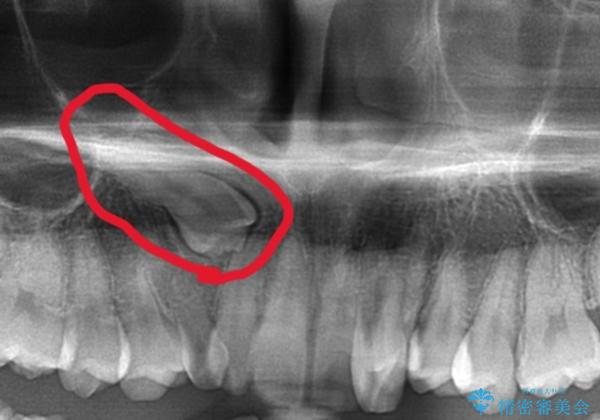

がたつきの強さから4本抜歯の必要性がありましたが、右上の歯は犬歯が一本埋まっており、乳歯がある状態でした。

右上については先に乳歯を抜歯して、犬歯が使えるようであれば第一小臼歯を抜歯することとして治療を開始しました。

当初、犬歯が動くようであれば代わりに小臼歯を抜歯する予定でしたが、

開窓して器具で力をかけても動く様子がなかったため抜歯とし、小臼歯を犬歯に見立てて治療を完了しました。

埋伏歯の抜歯について

当院では外科も行っておりますので、特に大学病院等に行かなくても埋伏歯抜歯のような難易度の高い治療を行うことができます。

それにより患者様の別病院での診察を受けなければならないといった負担も軽減して差し上げることが可能です。